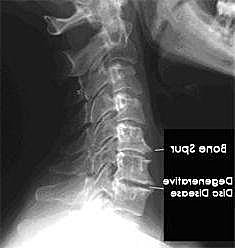

骨刺學名"骨質增生"是關節因退化而自行修補的正常現象,關節因種種原因造成軟骨的磨損、破壞,並促成骨頭本身的修補、硬化與增生,是一種自然的老化現象,一般長骨刺就表示此人的脊椎進入老化階段。然而,骨刺並非老人家的專利,由於工作型態改變,許多人必須久坐、久站,若是加上姿勢不正確,很容易年紀輕輕就使脊椎提早發生退化現象,而誘發骨刺的發生。

骨刺是脊椎退化過程中所伴隨的一種現象,隨著年齡的增長,人體的脊椎構造也會跟著退化,當骨頭與軟組織接壤的地方因長期承受壓力、拉力、損傷,造成脊椎與脊椎間的軟骨漸漸失去水分與彈性,致使骨骼出現退化性改變,這種骨骼退化性改變就會導致骨質增生,而形成骨刺。另外,反覆活動或不適當的運動,也常會使關節部位的骨骼及軟組織過度磨損,而長出骨刺。骨刺一般好發於活動較頻仍的關節,由於這些關節長時間反覆使用,因此很容易發生磨損與退化的現象。而身體容易誘發骨刺生長的地方包括頸椎、腰椎、膝關節、腳跟,另外,手指跟手肘也是骨刺容易發生的部位。